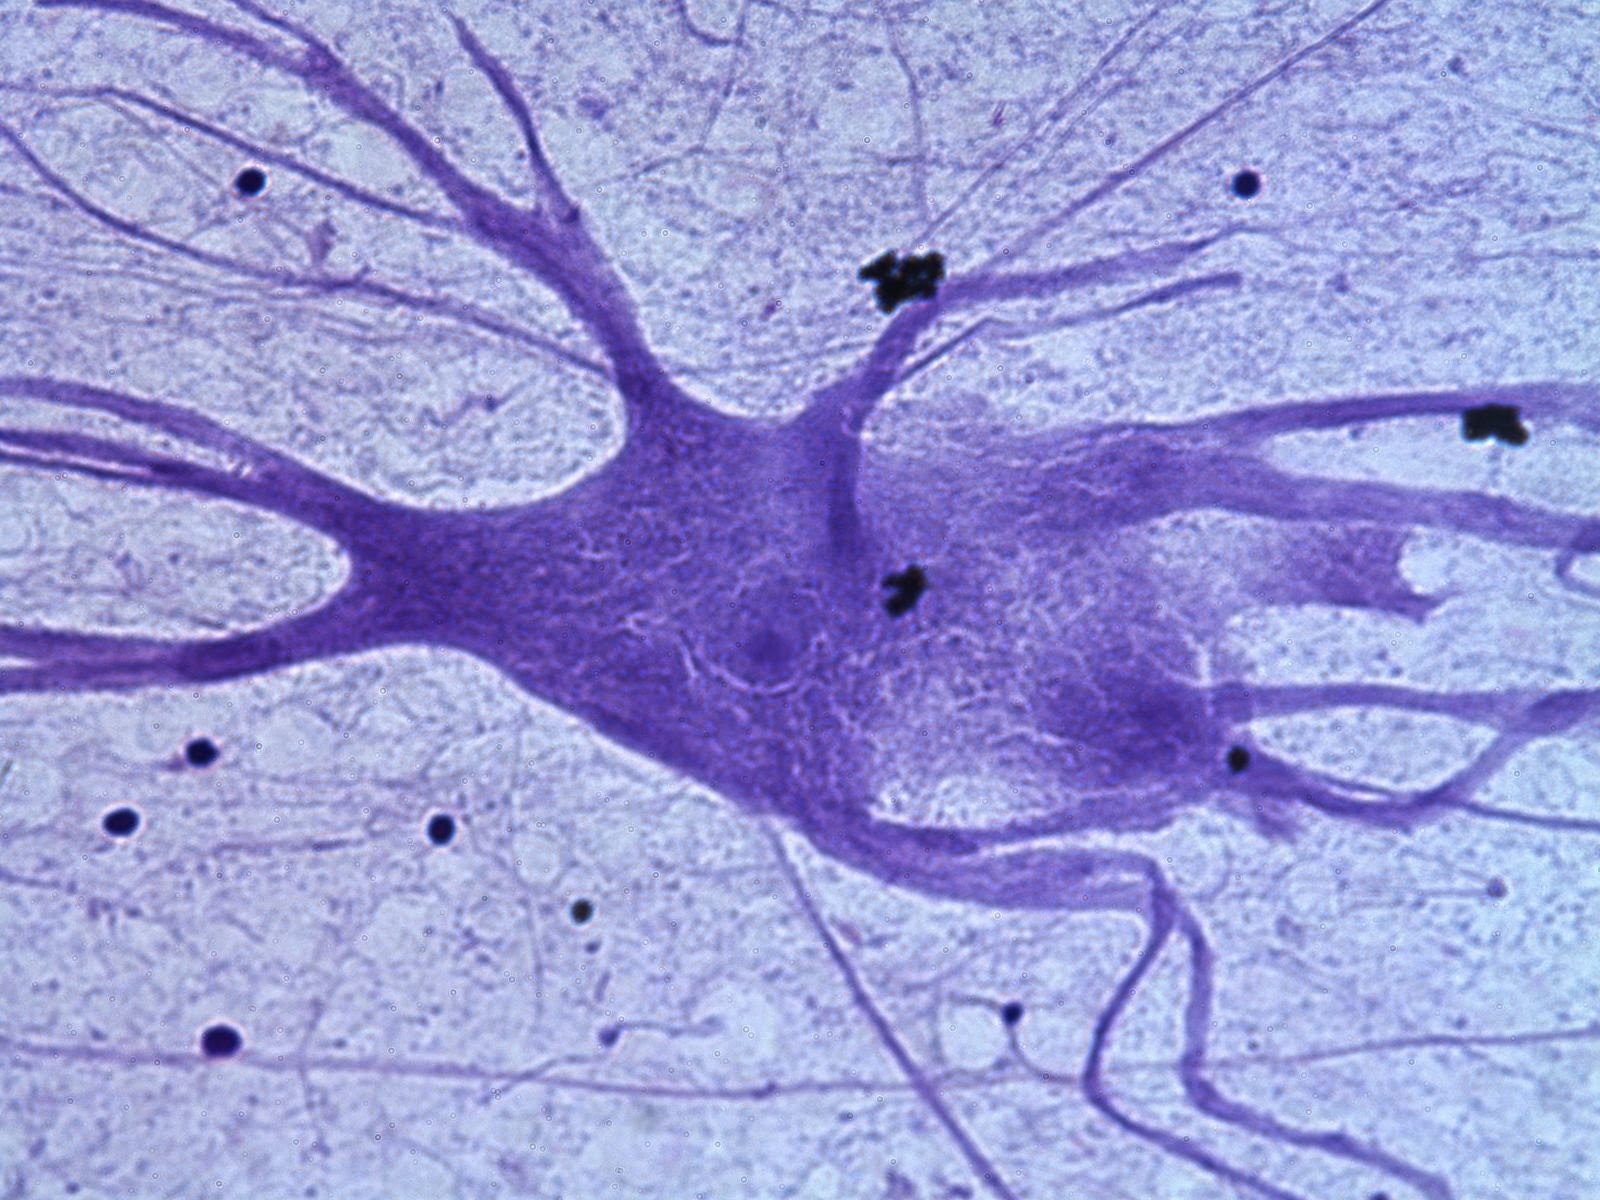

Al mecanismo fisiológico responsable de la

producción de la formación y desarrollo normal de las células sanguíneas en la

médula ósea, debido a su capacidad de permitir el anidamiento, el crecimiento y

la diferenciación de las células germinales hemopoyéticas, se denomina hematopoyesis.

Los tejidos que producen células sanguíneas son los tejidos hemopoyéticos, los

primeros tejidos de este tipo en el embrión humano se forman en el saco vitelino,

una membrana relacionada con todos los embriones de los vertebrados. Este saco

retiene su función hemopoyética y se forman grupos de células denominados islas

hemáticas, hacia la tercera semana del desarrollo humano, que producen

citoblastos primitivos que migran al propio embrión y colonizan la médula ósea,

el hígado, el bazo y el timo, donde los citoblastos se multiplican y dan lugar

a las células sanguíneas durante todo el desarrollo fetal.